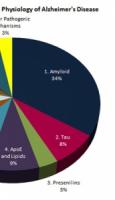

ALZHEIMER: Bloquer l'inflammation peut réduire les symptômes